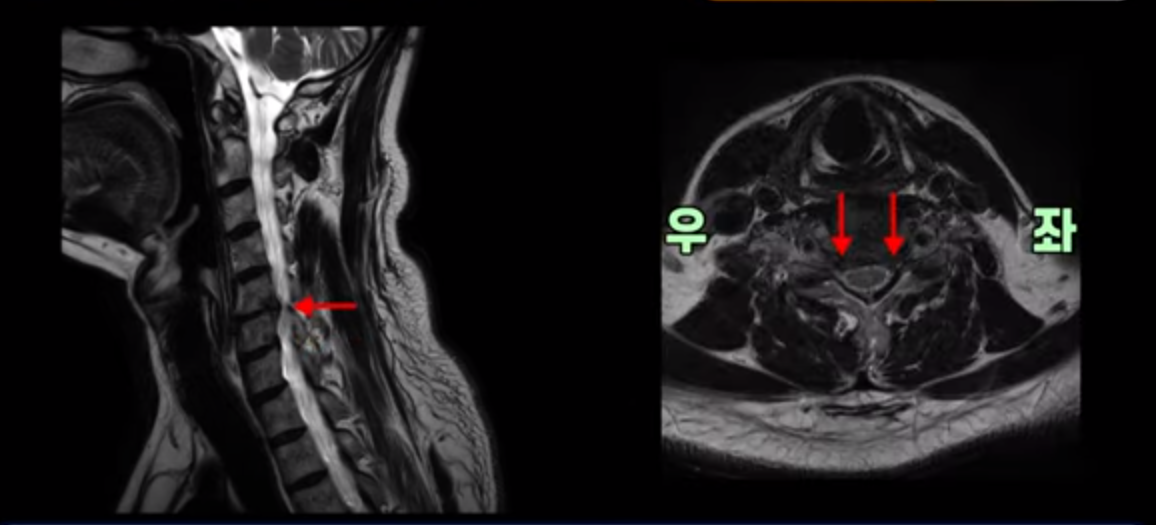

우선 이분 증상은 좌측 어깨와 팔 통증입니다. 이분 MRI를 보면 5번 6번과 6번 7번이 안 좋아 보입니다.

5번 6번에는 오른쪽과 왼쪽 모두 디스크 파열이 있고,

6번 7번에는 왼쪽으로 디스크가 밀려 나와 있습니다.

왼쪽으로 신경이 빠져나가는 추간공을 보면 보시다시피 5번 6번과 6번 7번 신경 구멍이 아래나 위에 비해 막혀있는 게 보입니다.

디스크도 밀려 나와 있고 협착도 있는 겁니다.